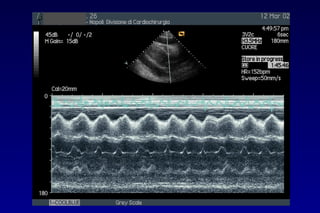

METODOLOGIA DI STUDIOMETODOLOGIA DI STUDIO

Il fluido tende a

raccogliersi

inizialmente

dietro la parete

posteriore del VSx

Man mano che

aumenta

la quantità del

versamento il foglietto

parietale diventa

immobile

METODOLOGIA DI STUDIO

L’accumulo di quantità

maggiori di liquido

determina l’estensione

dello spazio eco-privo

lungo il bordo laterale

del cuore e

anteriormente

fino a circondare

completamente le

cavità cardiache